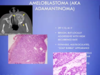

What patholgoy is shown in the provided images?

Describe the featues of each

Radiographically: “soap bubble”

Histologically : stellate reticulum, peripheral palisating (outside perpendicular to inside cells) with apical clear cytoplasm